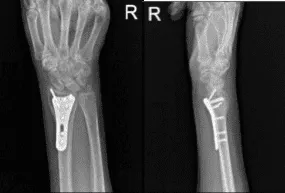

After two weeks, the patient checked in with a presented Xray and saw that osseous and metallic elements are in good alignment. Patient is still in splint but not taking any pain medications. In 4th week’s post operation, observed plate fixing the distal radius is again noted with screws holding the plate in good position.

In the 6th week, splint was discarded. Finally, on her 8th week’s post operative follow up, the patient is non tender to palpation along the wrist joint line distal to radius and has mild tenderness over the styloid process of ulna, and has some soft tissue swelling around the incision. The patient has no difficulty tolerating range of motion as well as stability testing.

AP and Lateral View of Patient RT 2 weeks Post-operative

AP and Lateral View of patient RT wrist 2 weeks Post-operative